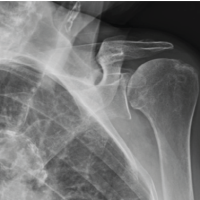

A 64-year-old female presented following a mechanical fall at work, reporting bilateral hip pain, more pronounced on the left side. The patient had no history of hip pain before the fall. Clinical examination demonstrated a preserved range of motion in both hips, with discomfort on weight bearing but no focal neurological deficit. Initial anteroposterior pelvic radiography demonstrated no acute fracture, but revealed a well-defined lucent lesion in the proximal left femur (Fig. 1). A computed tomography (CT) scan of the pelvis was subsequently performed to exclude an occult fracture. CT confirmed an elongated intramedullary lucent lesion within the proximal left femoral metaphysis, characterized by sclerotic margins without cortical destruction, endosteal scalloping, or an associated soft-tissue mass, suggesting a non-aggressive process (Fig. 2 and 3).

Figure 1: Anteroposterior pelvic radiograph demonstrating a well-defined lucent lesion in the proximal left femoral metaphysis (arrow), with no associated fracture.